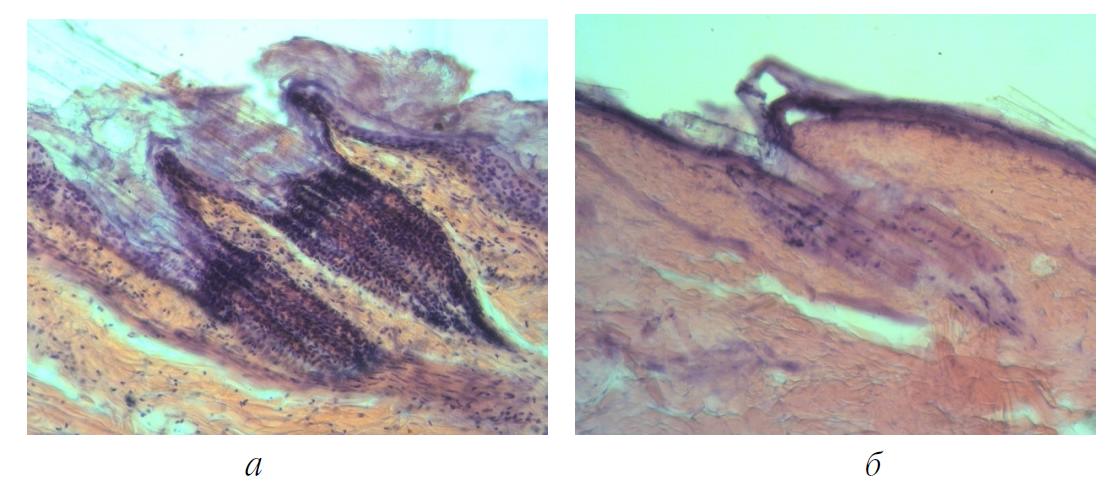

После термостатирования кожных эксплантатов во второй серии с использованием экранов из светонепроницаемой черной бумаги показатели жизнеспособности дермальных тканей оставались высокими и не отличались значимо от результатов опытов первой серии (рис. 3, а).

Рис. 3. Структура кожных эксплантатов: а – во II серии в группе с их экранированием черной бумагой от алюминиевой фольги. Хорошая сохранность ядер клеток эпителиального слоя, слоя собственно дермы и волосяных фолликулов; б – в III серии в группе с их экранированием тонким стеклом от алюминиевой фольги. Некротизирование волосяных фолликулов, эпителиального и собственно дермального слоев. Окраска гематоксилином и эозином, ув. × 100

В третьей серии опытов наметилась тенденция к снижению витальности в группе эксплантатов при их экранировании от кристаллов кремния тонким стеклом. Хотя снижение показателя жизнеспособности эксплантатов оказалось незначимым, лишь в части образцов некротические процессы в их мышечном слое стали несколько более выраженными. Местами поперечная мышечная ткань эксплантатов была некротизирована: определялись только контуры волокон без исчерченности и ядер. Между мышечными волокнами имелись разложившиеся соединительнотканные клетки, в некоторых местах были видны остатки их ядер. Однако в группе эксплантатов, экранированных от алюминиевой фольги тонким стеклом, наблюдалось резкое снижение их витальности, что фактически означало гибель дермальных тканей. Во всех без исключения образцах выявлялись обширные некротические процессы с захватом всех слоев дермы. Определялись только единичные прокрашиваемые пикнотичные ядра на фоне некротизированных волосяных фолликулов (рис. 3, б).